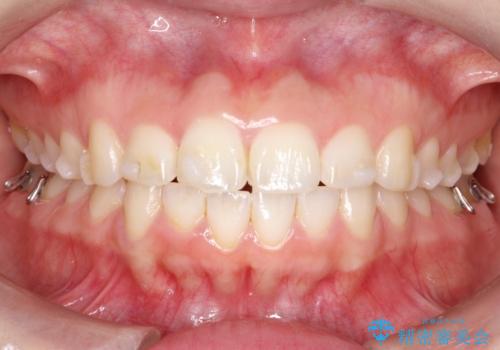

- 矯正装置

- 審美装置

- 患者様は、歯並びのガタガタ(重度の叢生)を改善したいとのことで来院されました。診察すると、歯列のスペース不足が著しく、前歯が重なり合い、噛み合わせにも影響が出ている状態でした。歯をきれいに並べるためには抜歯によるスペース確保が不可欠と判断し、上下の小臼歯4本を抜歯したうえで、目立ちにくい審美ワイヤー矯正(白いワイヤーと透明ブラケット)を用いた治療計画を立てました。

抜歯によって歯を動かすためのスペースを確保。その後、審美ワイヤー矯正を用いて歯を1本ずつ適切な位置に誘導しながら、噛み合わせのバランスも整えていきました。時間はかかりましたが、ガタガタの歯並びがきれいに整い、機能的にも審美的にも満足のいく仕上がりとなりました。患者様からは「歯並びが劇的に改善し、見た目だけでなく噛みやすさも向上した」と喜びの声をいただきました。